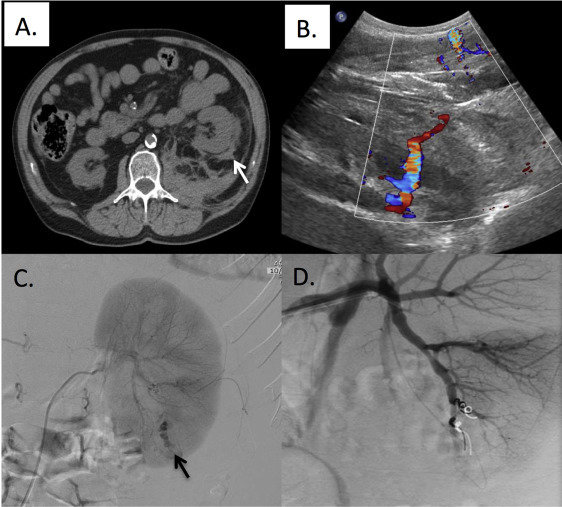

Biopsy

Indication

Preparation for Kidney Biopsy